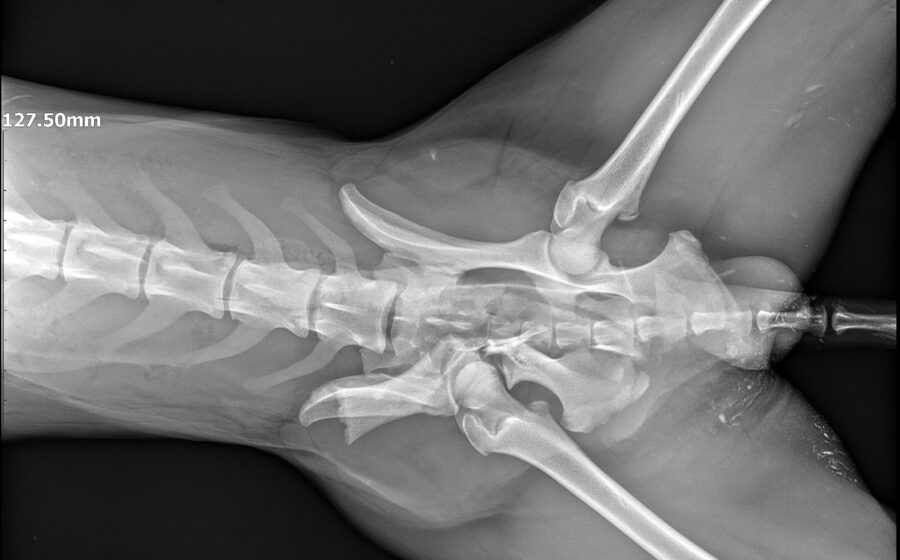

Seine Geschichte ist bewegend: Er wurde schwer verletzt am Straßenrand gefunden. Vermutlich wurde er hinter einem Auto hinterher geschleift und dann liegengelassen. Als Notfall wurde er in die Tierklinik gebracht, wo bei ihm drei Frakturen diagnostiziert wurden – am Darmbein, am Hüftgelenk und am Sitzbeinhöcker. In einer aufwendigen Operation, wurde die Darmbeinfraktur mit einer Platte fixiert. Die Hüftgelenksfraktur wurde nach Einholung zweier deutscher Ärzte-Meinungen nicht operiert, er hat einen Beckenengstand. Mit Physiotherapie wurde er soweit wieder aufgebaut, dass er jetzt mühelos 2 Stunden Spazierengehen kann. Er liebt die Bewegung und flitzt gerne durch den Garten seiner Pflegestelle.